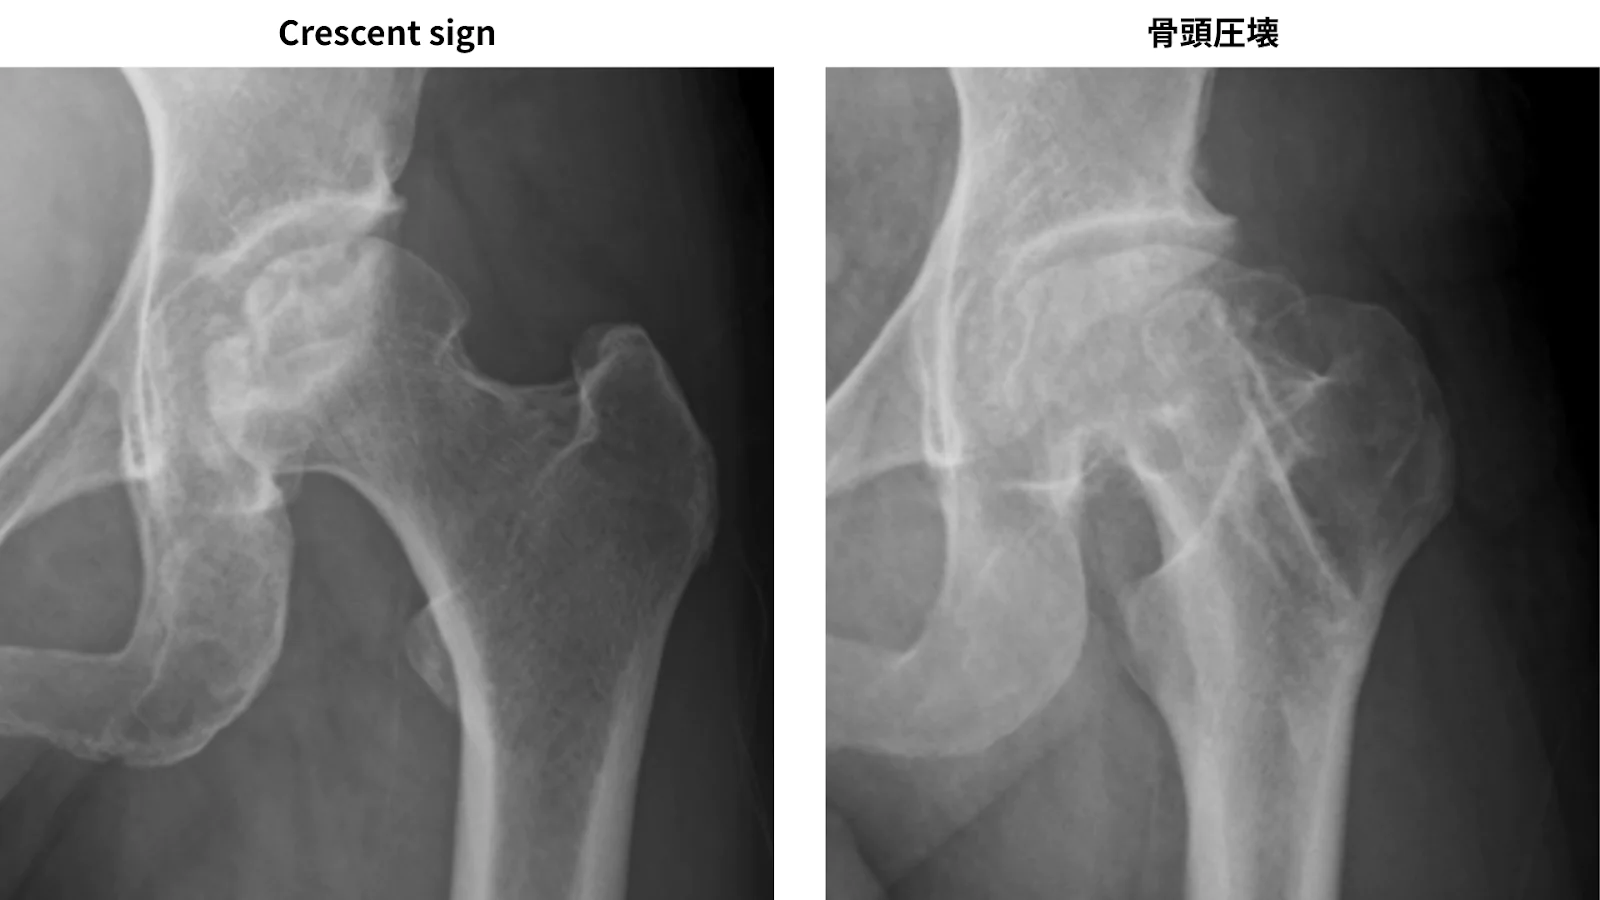

X線所見:

骨頭圧潰や「crescent sign」と呼ばれる骨頭軟骨下骨折線像を確認。